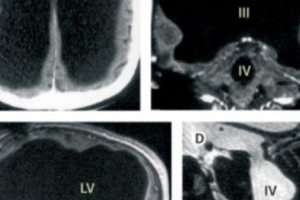

У мужчины сильно расширены боковые, третий и четвертый желудочки, а также очень тонкий кортикальный слой. Другими словами, спинномозговая жидкость, которая в норме циркулирует по мозгу и выводится в кровеносную систему, заполнила почти весь череп, оставив лишь небольшую часть мозгового вещества.